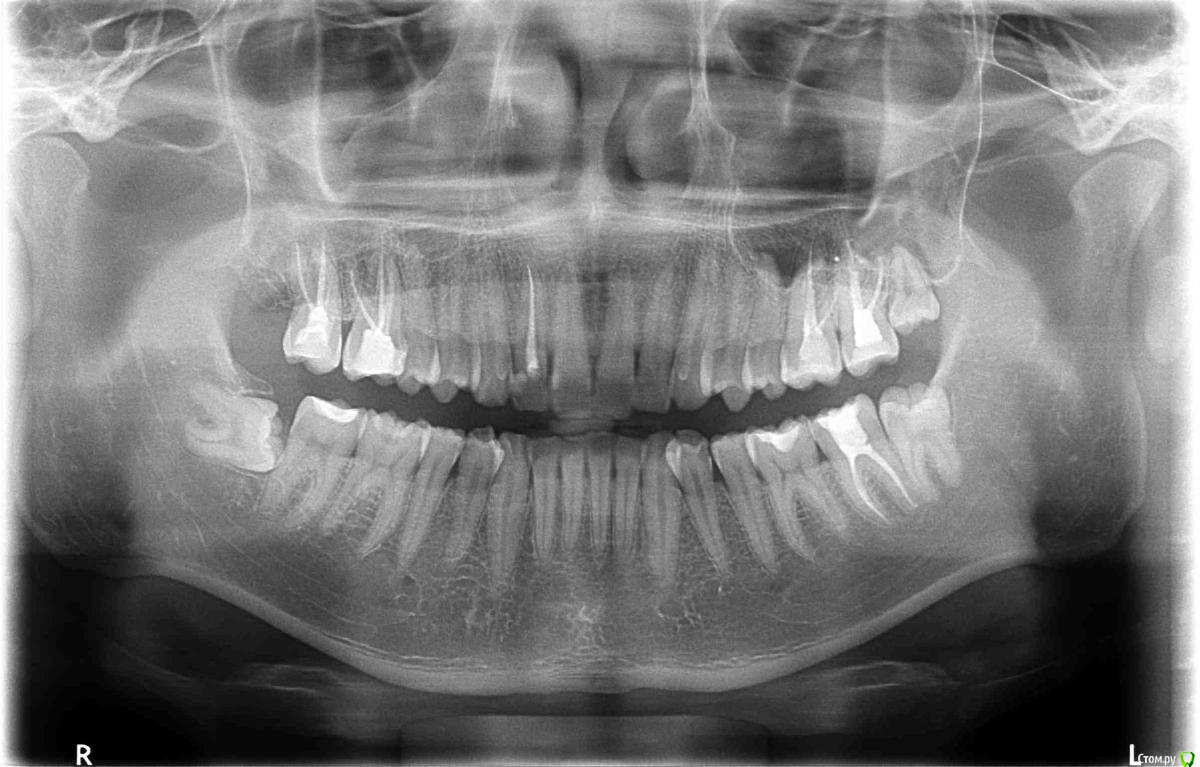

St. Опубликовано 22 декабря, 2015 Поделиться Опубликовано 22 декабря, 2015 От холодного зуб без нервов болеть не может - если нерва нет, то реагировать там на холод и тепло нечему. При постукивании и накусывании после недавнего лечения каналов какое-то время может оставаться чувствительность, обычно до 2 недель, но бывает немного дольше, это нормально.По Вашему снимку я бы рекомендовала обязательно и в ближайшем будущем удалить зуб мудрости внизу справа, полечить кариес в 34(следующий за клыком внизу слева). И когда зуб перестанет реагировать на постукивание - одеть на него коронку и обсудить необходимость коронок на другие боковые зубы без нервов. 1 Ссылка на комментарий

bozz903 Опубликовано 19 марта, 2016 Автор Поделиться Опубликовано 19 марта, 2016 Здравствуйте. С наступлением весны все тот же 16 зуб стал реагировать на температуру очень сильно. Также ноет сам по себе периодически. Боль не похожа на гиперчувствительность эмали.Сделал новые снимки. Что нибудь можно сказать по сравнение с теми, которые прикреплены в первом моем сообщении? Ссылка на комментарий

DmitrySH Опубликовано 19 марта, 2016 Поделиться Опубликовано 19 марта, 2016 (изменено) Низкая информативность снимков. Даже на ОПТГ качество лучше Изменено 19 марта, 2016 пользователем DmitrySH Ссылка на комментарий